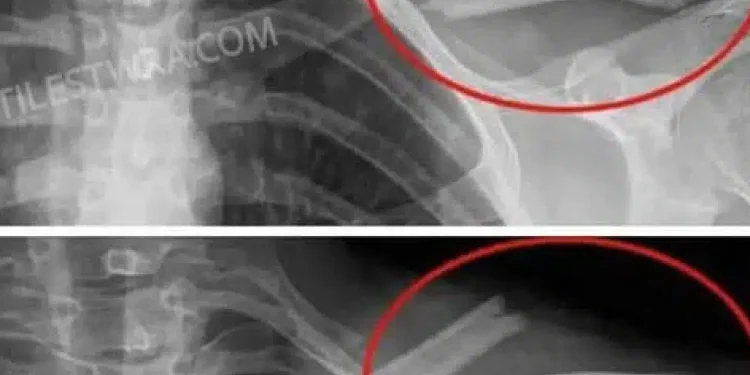

Αποδυναμώνουν τα οστά: Η υψηλή πρόσληψη νατρίου που περιέχουν πολλά από αυτά , μειώνει το ασβέστιο, αυξάνοντας τον κίνδυνο οστεοπόρωσης.